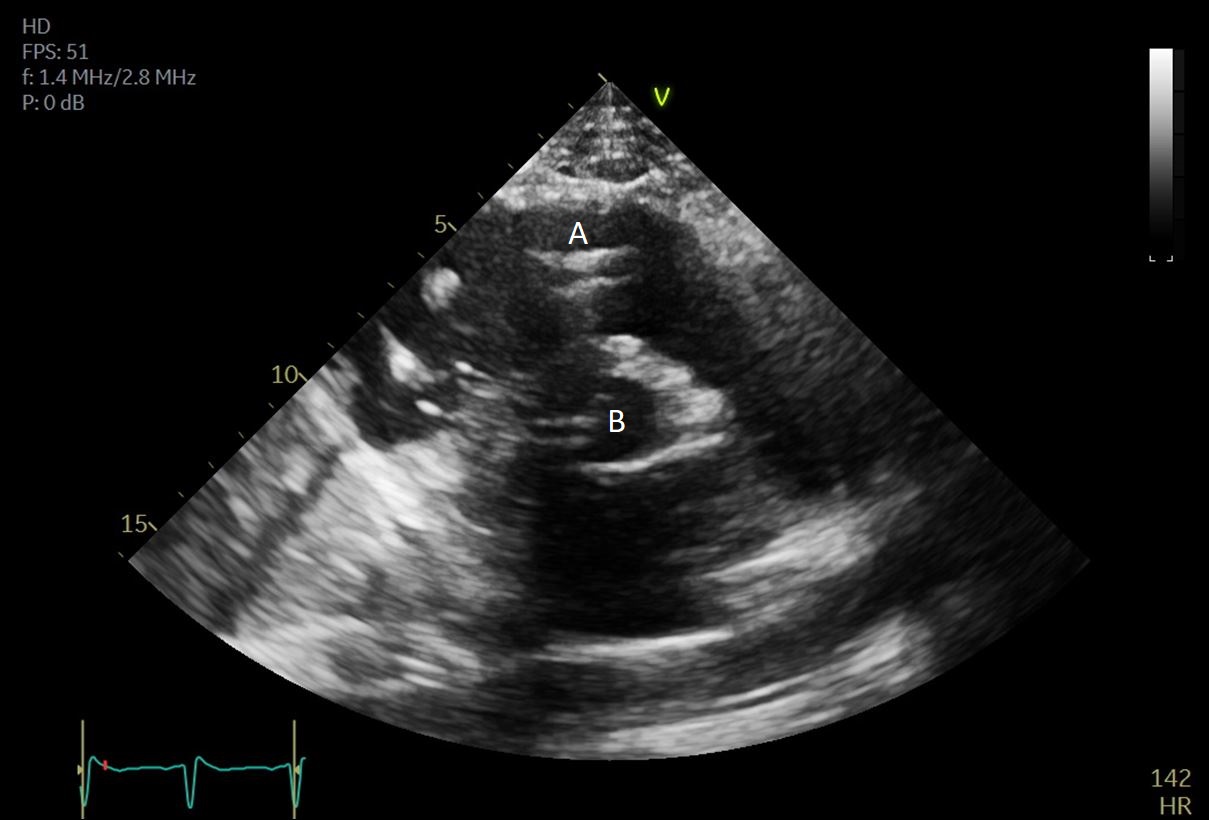

Impella (A) in the LV cavity caused disruption and damage to subvalvular apparatus resulting in flail segment (B) of the mitral valve.

Fig. 4.Impella (A) placement causing disruption and damage to subvalvular apparatus resulting in mitral valve flail (B) and mitral regurgitation (C).